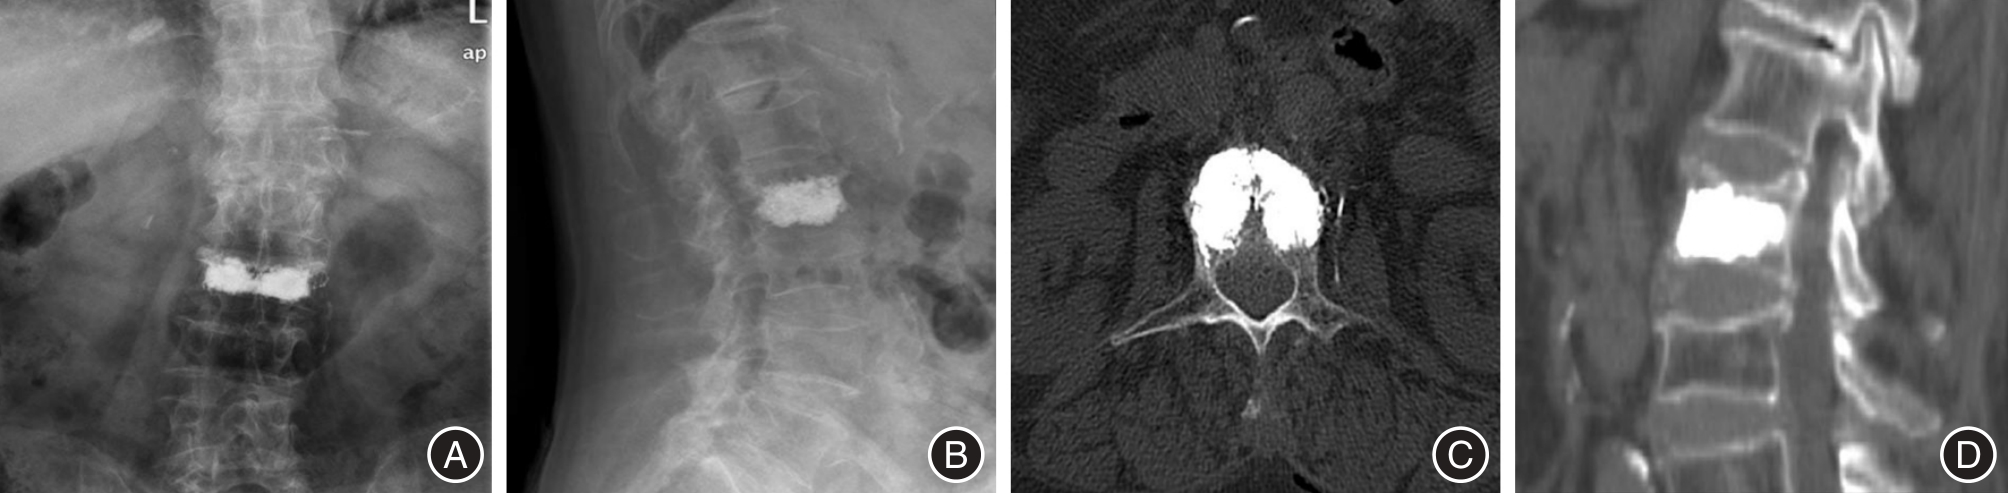

目的 探究经皮椎体成形术(PVP)治疗骨质疏松性椎体骨折(OVF)后早期残余腰背痛的影响因素,为临床干预提供依据。 方法 回顾性分析2020年7月至2025年6月接受PVP治疗的1 120例OVF患者,筛选出61例术后早期(术后2 d至1个月)残余腰背痛患者(术后VAS评分> 3分,观察组),采用1∶1匹配原则(按年龄± 5岁、术前骨密度± 0.5SD)选取61例对照,进行单因素及logistic回归分析。 结果 单因素分析显示,术前胸腰筋膜损伤(TFI)、患椎MRI液化信号、责任椎体数(≥ 2个)及骨水泥分布不佳在两组间差异有统计学意义(P < 0.05);多因素回归表明,上述因素为独立危险因素(OR值分别为5.378、6.111、3.245、2.890,P < 0.05)。模型AUC为0.929,提示预测效能良好。 结论 术前TFI、患椎MRI液化信号、多责任椎体及骨水泥分布不佳可能增加PVP术后早期残余腰背痛风险。

Objective To investigate the factors influencing the persistence of residual low back pain following percutaneous vertebroplasty (PVP) in patients with osteoporotic vertebral fractures (OVF), in order to provide a scientific basis for clinical intervention strategies. Methods A retrospective analysis was conducted on data from 1 120 patients diagnosed with OVF who received PVP treatment between July 2020 and June 2025. Among them, 61 patients who experienced residual low back pain in the early postoperative period (defined as 2 days to 1 month after surgery) with a postoperative visual analog scale (VAS) score greater than 3 points were selected as the observation group. An additional 61 control subjects were matched to the observation group at a 1∶1 ratio based on age (± 5 years), gender, and preoperative bone mineral density (± 0.5 standard deviation). Univariate and logistic regression analyses were subsequently performed to evaluate potential influencing factors. Results Univariate analysis revealed statistically significant differences between the two groups with respect to preoperative thoracolumbar fascia injury (TFI), MRI-detected liquefaction signals in the affected vertebrae, the number of involved vertebrae (≥ 2), and suboptimal bone cement distribution (P < 0.05). Multivariate regression analysis confirmed that these factors were independent risk factors, with corresponding odds ratios (ORs) of 5.378, 6.111, 3.245, and 2.890 (all P < 0.05). The area under the curve (AUC) of the predictive model was 0.929, indicating a high level of predictive accuracy. Conclusion Preoperative TFI, MRI-demonstrated liquefaction signals in the affected vertebrae, the presence of multiple responsible vertebrae, and suboptimal bone cement distribution may contribute to an increased risk of early residual low back pain following PVP.